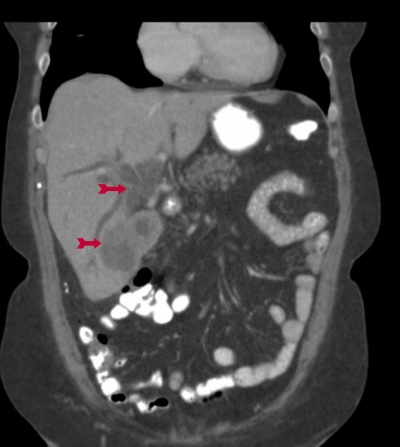

או טומוגרפיה ממוחשבת. CT בטן יכול להדגים את השאת בכיס המרה (תצלום 47.8) באם היא פורצת לכבד (תצלום 48.8) או מערבת בלוטות (רגישות נמוכה).